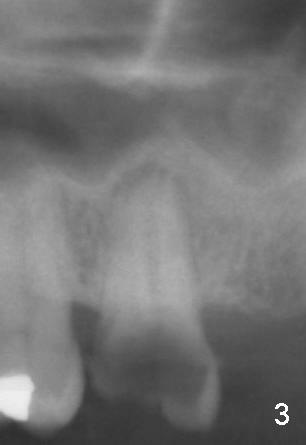

A 52-year-old black man fails to return to finish root canal therapy for the tooth #15; ultimately it is non-salvageable (Fig.1-3). The tooth has 3 basically fused roots (Fig.4 black (buccal) and red (palatal) outlines), above which is the sinus septum (*). By inserting an immediate implant into the sinus septum, primary stability should be high (Fig.5 vs. 6).